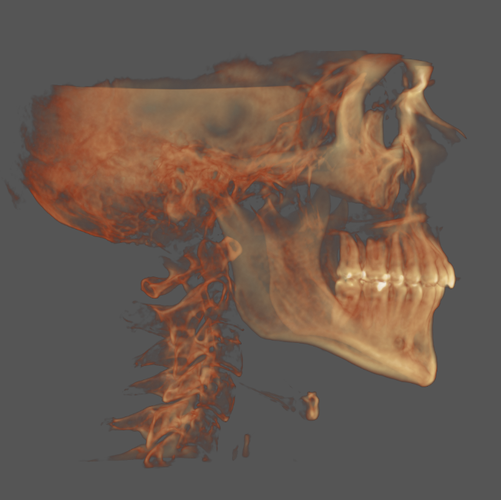

I'm currently 22 and have a recessed mandible, maxilla and narrow palate, all of these are not severe but add up, this has lead to mild sleep apnea, TMJ, and migraines.

I'm currently 22 and have a recessed mandible, maxilla and narrow palate, all of these are not severe but add up, this has lead to mild sleep apnea, TMJ, and migraines.